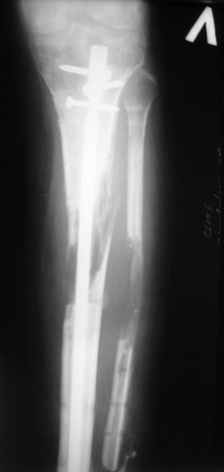

Ерсин, мы тоже имеем опыт такой фиксации. Подобную операцию за последние 3 года мы сделали трем пациентам. Снимки одного из них я прилагаю.

К сожалению, ни в одном из этих 3-х случаев мы не получили удовлетворяющего нас результата. Очень трудно провести штифт, введенный антеградно ровно по центру таранной кости. Отсутствие подвижности между диафизом и дистальным отломком большеберцовой кости (после фиксации в аппарате в течение 1-2 мес) очень усложняет проведение штифта в центр блока таранной кости. Поэтому мы от этого пока отказались, и проводим штифт через пятку. При данном варианте фиксации подобных проблем не возникало ни разу.

Больному выполнена резекция малоберцовой кости, ВХО раны, сближение отломков. Резекция м\б через отдельный разрез. После ВХО компрессия в аппарате, края раны сближены наводящими швами (без натяжения).

В случае гладкого заживления раны, при условии положительного решения вопроса с металлом, планируем перемонтаж аппарата Илизарова, дополнительную резекцию дистального отломка, выведение полокости голеностопного сустава в правильное положение (см. боковую Р-грамму), одномоментно остеотомия большеберцовой кости. После восстановления длинны голени, по всей видимости, артродез голеностопного сустава.

Рентгенограммы прилагаются. Фото местного статуса выложу в ближайшее время.